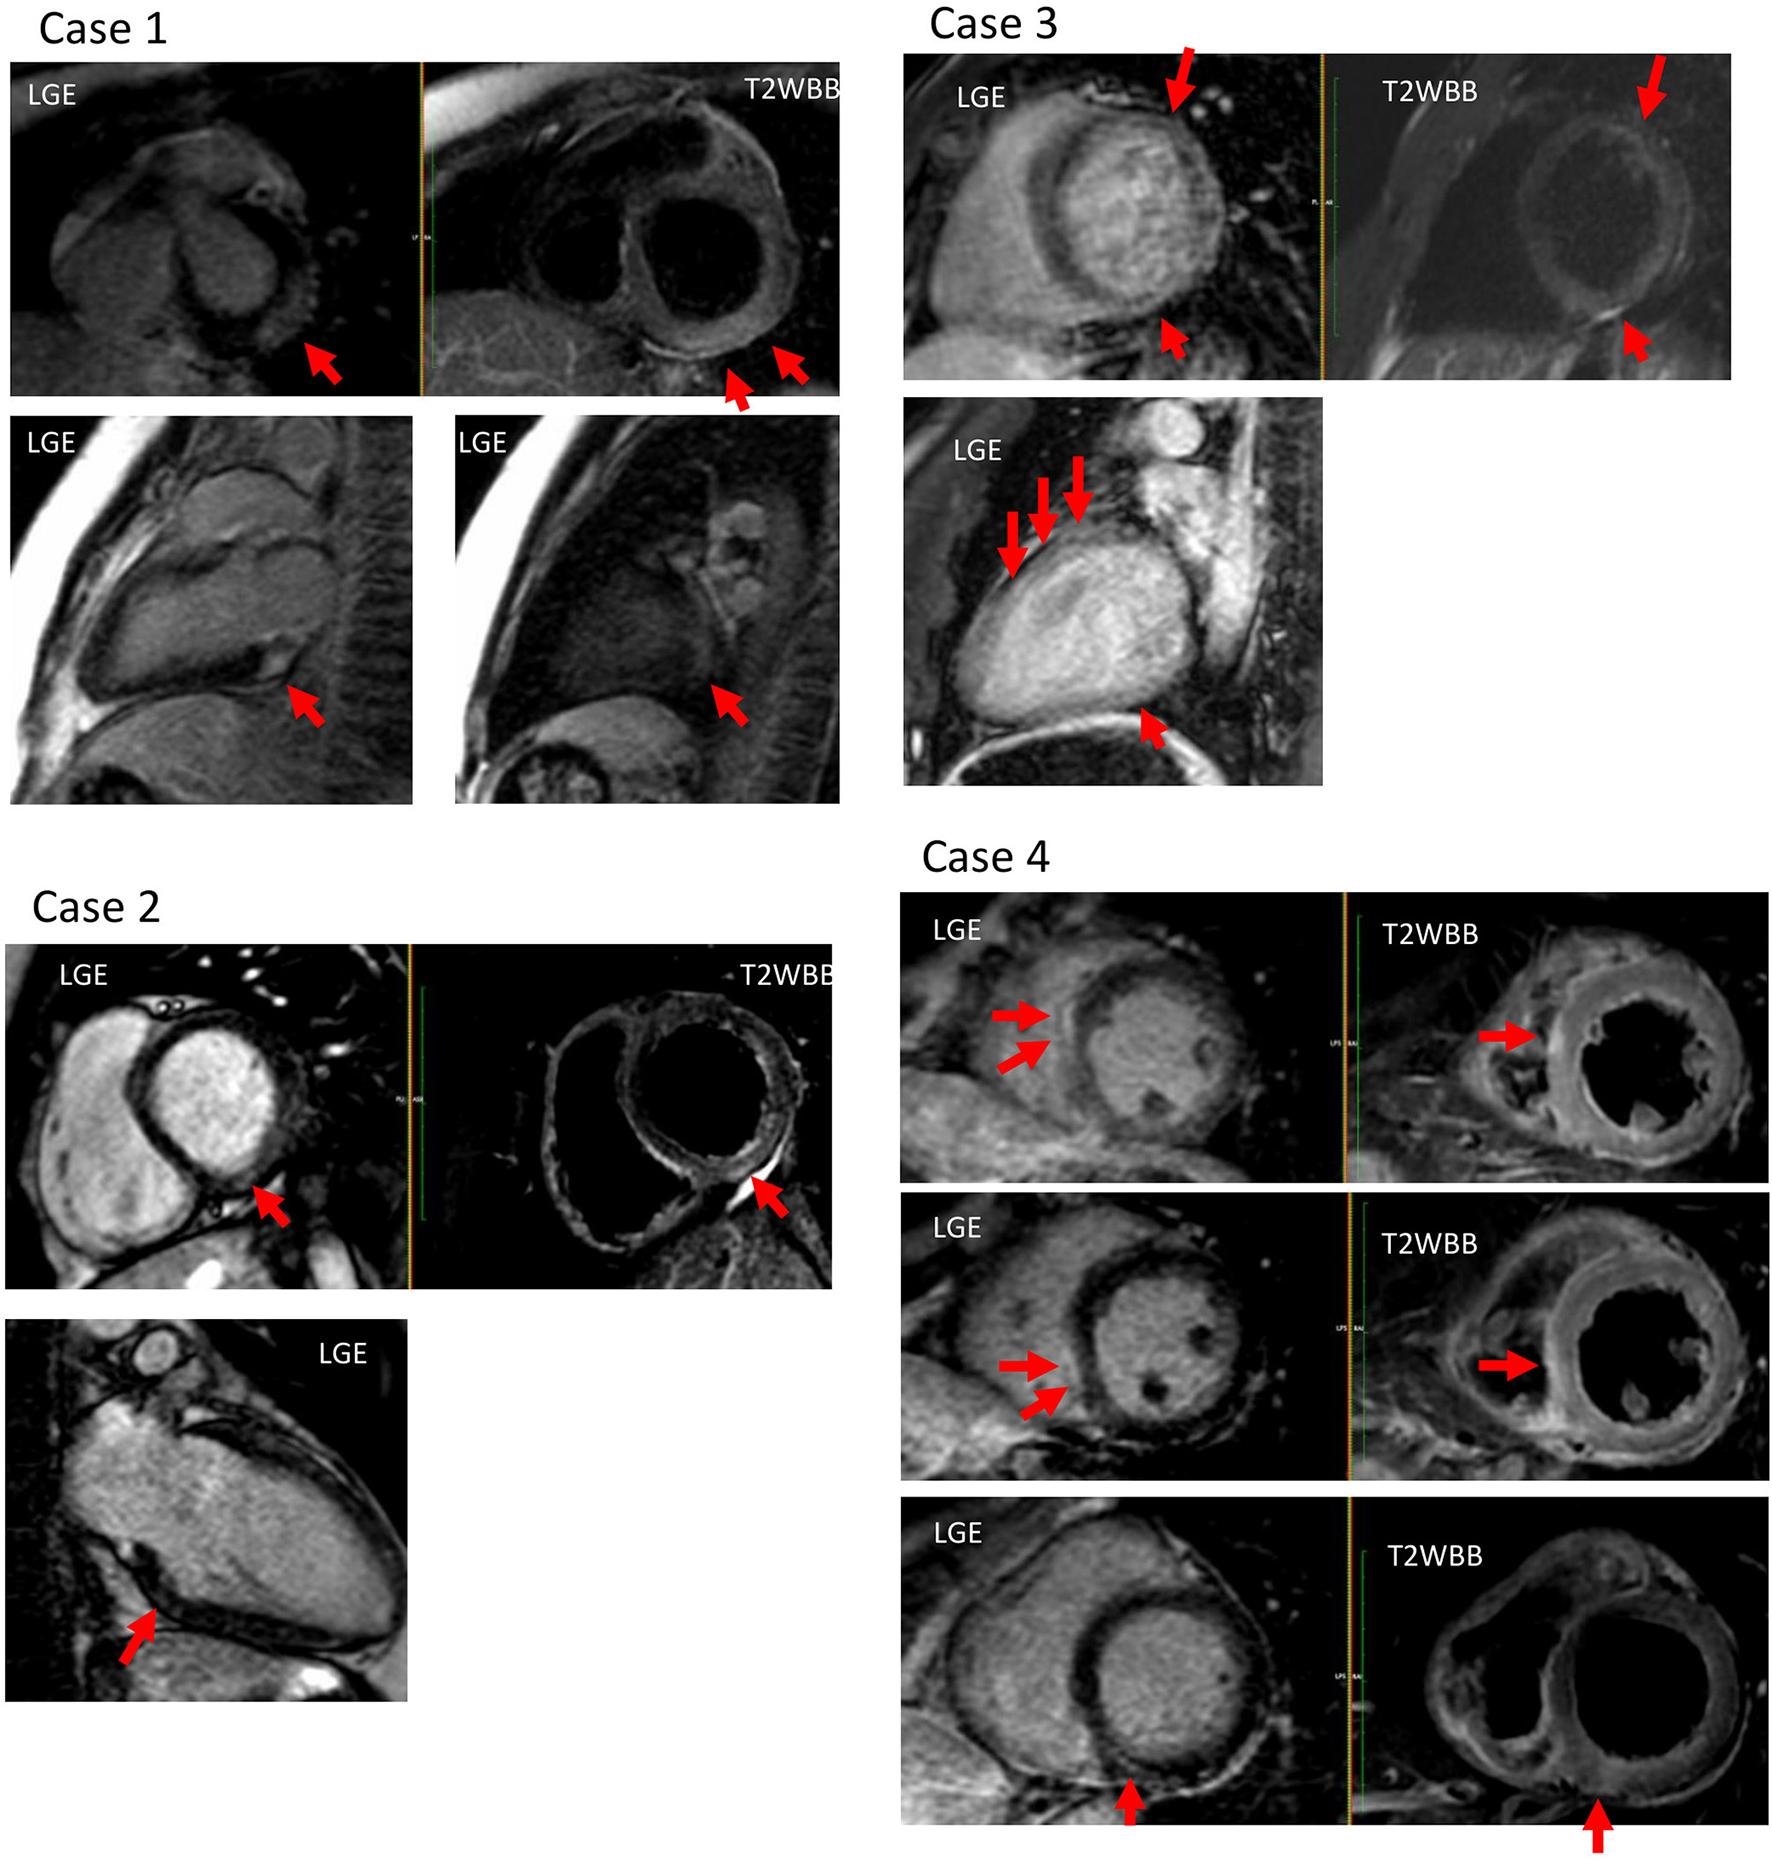

Figure 1

Cardiac magnetic resonance imaging (MRI) of all profiled cases. Case 1: T2 high signal intensity and late-gadolinium enhancement (LGE) were observed at the sub-epicardial wall of the basal-mid inferolateral left ventricular (LV). Case 2: T2 high signal intensity and LGE were observed at the mid wall of the basal inferior LV. Case 3: T2 high signal intensity and LGE were observed at the mid wall of the anterior, and at the inferior LV. Case 4: T2 high signal intensity and LGE were observed at the mid-wall of basal inferior, and at the sub-epicardial wall of the mid- and inferoseptum LV.